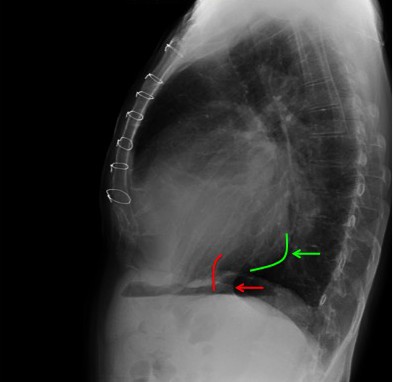

CASO: Paciente oncológica con disnea.

Hallazgos:

- Ademas de un catéter reservorio subcutáneo, se observa un derrame pleural izquierdo.

¿Cómo sabemos qué es izquierdo y qué es derecho si solo disponemos de una placa lateral? Pues bien, podemos definir tres signos:

Signo de la costilla grande: recordemos que la placa lateral normalmente se realiza con la parte izquierda del paciente pegada al chasis radiográfico. Por tanto esta parte es más posterior y así se ve más grande en la imagen de placa simple después de incidir el rayo x. Si observamos mejor, vemos como el derrame llega hasta las costillas del lado en el que son más pequeñas, las izquierdas, por tanto es en este lado donde se localiza el derrame.

Signo del desplazamiento vertical: por la misma razón, las costillas derechas se ven más separadas entre sí que las izquierdas, que están menos magnificadas.

Burbuja de la cámara gástrica: se posiciona bajo el hemidiafragma izquierdo.

Comprobemos con la placa PA: